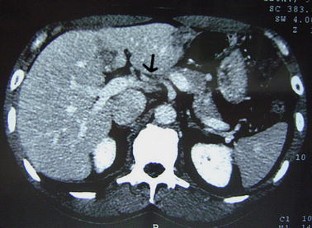

A variation in liver vascularization was discovered in a 50-year-old man. A single common hepatic artery was found to be responsible for vascularization of the entire liver. This artery was unusual in that it formed the first branch of the superior mesenteric artery, crossing the portal trunk shortly after its origin, and passed in front of the portal vein to reach the hilum of the liver, where it divided into a right and a left branch. This artery was a true common hepatic artery because a gastroduodenal artery emerged from it 2 cm after its origin. A common hepatic artery originating from the mesenteric artery and passing in front of the portal vein has never been described before. The patient had a second anatomical variation: the left gastric artery and the splenic artery arose directly from the aorta, without celiac trunk separation. This observation confirms the importance of carrying out a precise vascular assessment before all types of hepatic or pancreatic surgery, to identify possible variations in the number or trajectory of hepatic arteries.

Fig. 2